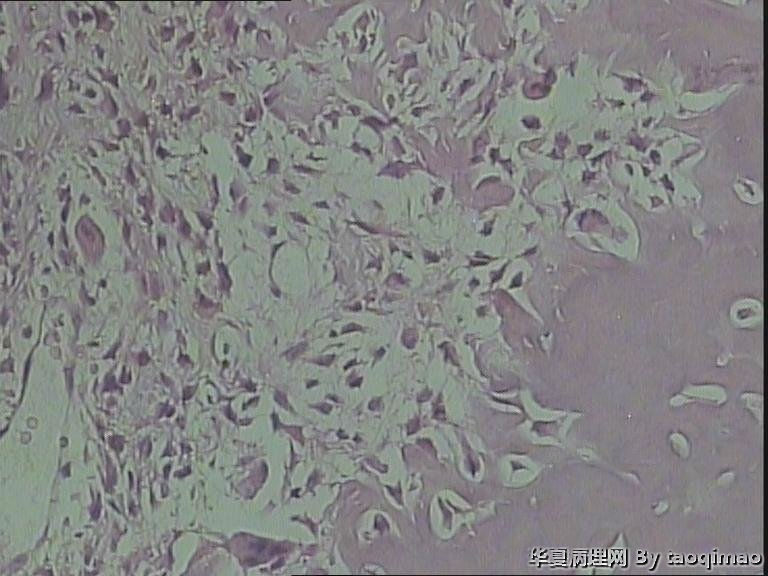

• 肋骨肿物,求助图1

这是比较容易取下来的部分,肋骨内部的肿瘤还在制片中

这是一部分容易取下来的肿瘤,其余部分还在脱钙中

患者女,31岁,胸部CT第八肋骨肿瘤,肿物在肋骨内突出骨外膜,大小2.3X1.5.切面灰白质韧

骨母细胞瘤。矿化不均要除外骨母细胞型骨肉瘤,虽然肿块小了点。还是找找核分裂,看看X线的好。